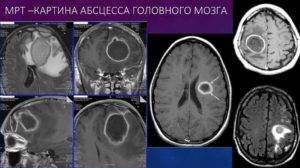

Абсцесс головного мозга

Картина весьма типична: объемное образование головного мозга, которое не оттесняет окружающие ткани, имеет сниженную плотность, относительно окружающей нервной ткани. Четко определяется капсула вокруг очага, особенно при контрастном усилении. В анамнезе чаще всего есть указание на перенесенный энцефалит.

Причиной образования абсцессов чаще всего являются воспалительные процессы в легких (бронхоэктатическая болезнь, эмпиема плевры, хроническая пневмония, абсцесс легкого)